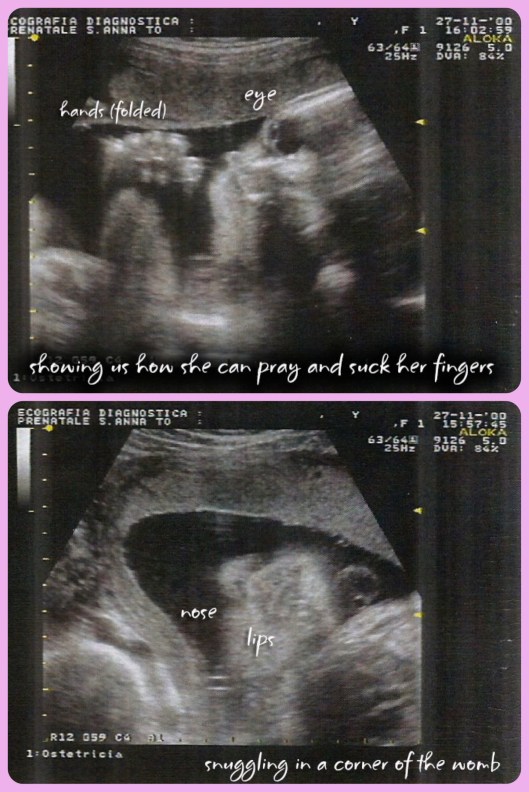

Of course that was all wonderful to hear, but there were some really fun moments of just watching her and being enamored by the littlest things she did. One of our favorites was when we saw her face and she seemed to purse her lips as if blowing us a kiss. Then we got a look at her profile and she had her hands folded together as if she was praying. So sweet! Soon after that she took her hands and put them to her face and we saw her little lips moving; she was sucking on her thumb (or fingers)! A little later as I kept staring at the screen, she turned to face the camera as if to say hi and show off her pretty features. Here are some pictures so you can see for yourself!

Isn’t she adorable? It’s hard to believe she will likely be in my arms in two months! Then we’ll be able to post pictures in full color…when we’re not too busy cuddling her (feeding her, changing her, or trying to get naps)!